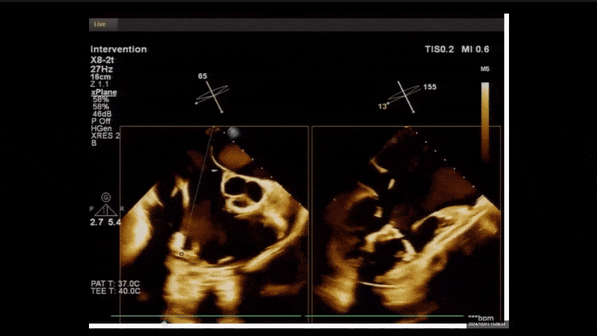

術(shù)中經(jīng)食道超聲輔助下可見LuX-Valve Plus夾持件抓捕瓣葉狀態(tài)良好,夾持件在位,室間隔錨定位置良好,假體瓣膜整體錨定狀態(tài)穩(wěn)固。

術(shù)后三維超聲

術(shù)后即刻經(jīng)食道超聲可見,三尖瓣假體瓣膜位置合適,牛心包瓣葉運(yùn)動狀態(tài)良好,開閉正常,瓣周及瓣葉對合緣處未見明顯返流,心電圖及心包狀態(tài)較術(shù)前無明顯變化。